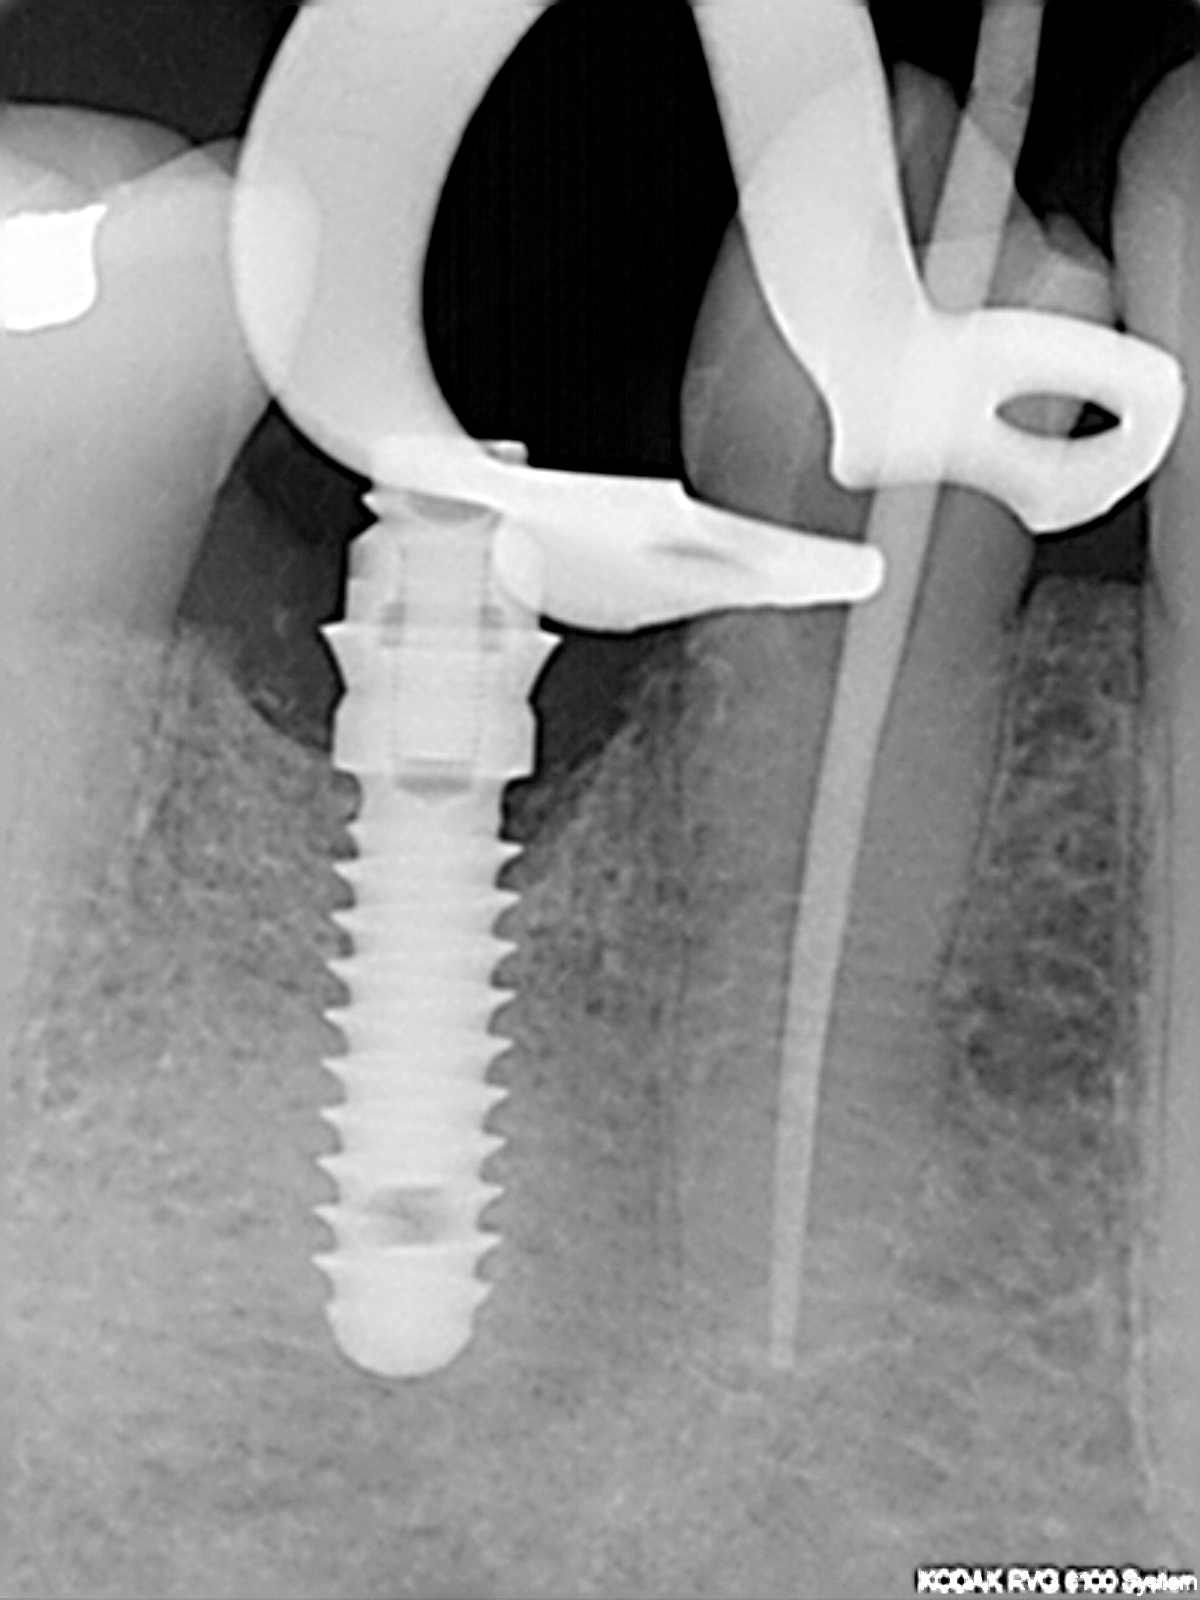

R2

1200 × 1600

Endorevision

Messaufnahme